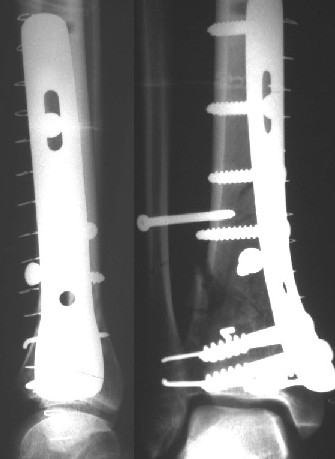

Нашел в комп-ре схожий случай:

1) з/репозиция, 2) фиксация 2 спицами, 3) аппарат, 4) фиксационные

спицы удалены...

См. аттачт.

А можно было наложить аппарат и по поводу ложного сустава...

По крайней мере не было бы укорочения (пусть и в 2 см)...